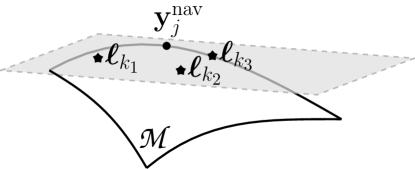

This paper follows the manifold-learning path and serves a two-fold objective: i) Present a machine-learning framework, the bi-linear modeling of data manifolds (BiLMDM), that contributes novelties to exploiting local and latent data structures via a sparsity-aware and bi-linear optimization task; and ii) apply BiLMDM to the dMRI-data recovery problem. In a nutshell, BiLMDM can be described as follows. Each vector of data, observed from an undersampled dMRI temporal frame, is modeled as a point onto or close to an unknown manifold, embedded in a Euclidean space. The only assumption imposed on the manifold is smoothness [40]. Landmark points are chosen to concisely describe the observed data-vector cloud, and are mapped to a lower-dimensional space, as in [34, 41], to effect compression and enable low-computational footprints in the proposed algorithmic solutions. Motivated by the smooth-manifold hypothesis, the proposed work approximates each data vector as an affine combinations of neighboring landmark points (cf. Fig. 2). A locally bi-linear factorization model, novel for data representations, is then formed to model/fit the point cloud: One factor gathers the coefficients of the previous affine combinations of the landmark points, while the other one serves as the linear decompression operator that unfolds the points back to the image dimensions. Improving on our preliminary results [42], a highly modular bi-linear optimization task is tailored to the dMRI-data recovery problem, penalized by terms which account for sparsity along the temporal axis and other modeling assumptions. A successive-convex-approximation algorithm is proposed to guarantee convergence to a stationary solution of the previous bi-linear optimization task.

The proposed work is validated against the following state-of-the-art schemes: Partially separable sparsity aware model (PS-Sparse) [18], joint manifold learning and sparsity aware (MLS) framework [34], smoothness regularization on manifolds (SToRM) [22], low rank and adaptive sparse signal model (LASSI) [23] and extra dimensional golden angle radial sparse parallel (XD-GRASP) [24]. In spite of sharing with the previous state-of-the-art schemes the principle of identifying low-dimensional structures for high-dimensional data and exploiting this structure to reconstruct data, BiLMDM’s original contributions in data approximations can be summarized as follows: i) BiLMDM departs from the mainstream manifold-learning approach of identifying a data-graph Laplacian matrix that penalizes an optimization (data-recovery) task as in [31, 22, 35], and uses instead the fundamental geometric principle of tangent spaces of smooth manifolds to search for data dependencies/patterns through local affine combinations of landmark points (cf. Fig. 2); ii) it offers a novel bi-linear factorization model, where one linear factor captures the local smoothness of the manifolds, via local affine combinations, while the other one accounts for the linear decompression operator which maps the low-dimensional affine approximations back to the high-dimensional raw-data/input space. The affine combinations and the decompression operator are jointly identified via a highly modular non-convex data recovery task, which may accommodate also additional prior information, e.g., periodicity over the temporal axis of the dMRI data. Unlike the traditional bi-linear schemes, BiLMDM doesn’t follow the classical dictionary learning approach of decomposing the image into two components as discussed earlier and model the dynamic foreground of the image as a sparse combination of adaptive dictionary atoms (which act as image basis) of MR image signals. A more detailed description of the differences of BiLMDM with the state-of-the-art dMRI recovery schemes is deferred to Sec. III. The efficacy of BiLMDM was observed on both synthetically generated and experimentally acquired cardiac cine MR data, undersampled via both Cartesian and radial trajectories. BiLMDM has consistently outperformed all the competing techniques and produced reconstructions which were sharp, free of undesirable artifacts, deformations and temporal bleeding.

For example, the most well-known case of is a linear subspace, which is the main hypothesis behind principal component analysis (PCA). PCA assumes that the data lie close to or onto a linear subspace in a low-dimensional space. Along the same lines, based on As. 1 and the concept of the tangent space of a smooth manifold, it is conceivable that neighbouring landmark points cooperate affinely to describe vector (the gray-colored area in Fig. 2 depicts all possible affine combinations of ). In other words, every temporal frame is approximated by a combination of landmark points, where these landmark points can be viewed as a representative of a particular group of frames sharing similar phase and motion characteristics. Upon defining the matrix , the above notion can be established by the existence of an vector that renders the approximation error small, where denotes the standard Euclidean norm of space . Since affine combinations are desirable, is constrained to satisfy , where stands for the all-one vector and superscript denotes vector/matrix transposition. Moreover, motivated by the low-dimensional nature of (As. 1), only a few landmark points are considered to cooperate to represent in its closed vicinity, i.e., is sparse. The previous arguments are summarized into the following modeling hypothesis.

The proposed scheme shares with PS-Sparse [18], SToRM [22], (and its other variants bandlimited-SToRM [31], navigator-less SToRM [35]) and MLS [34] similarities in terms of using navigator lines to learn the underlying data manifold. Instead of using the eigen vectors of the co-variance (PS-Sparse) and Laplacian (SToRM and its variants) matrices as the temporal basis, BiLMDM relies on robust sparse embedding [41] to estimate a low dimensional latent structure. SToRM and BiLMDM both aim at learning the structure of “smooth” data manifolds. Smoothness in SToRM is established globally over the data cloud by penalizing the recovery task via several operator norms of a graph-Laplacian matrix. On the other hand, BiLMDM enforces smoothness locally over the manifold via neighborhoods and affine approximations (patches) of the tangent spaces (cf. Fig. 2), and the data manifold can be viewed as an approximation of the union of all those patches (as discussed in As. 2). PCA-inspired schemes, such as PS-Sparse, search also for local affine/linear patches to manifolds. Nevertheless, BiLMDM does not impose any orthogonality constraints on any of its factors and , as PCA via the singular value decomposition (SVD) does. Identification of landmark points to learn an underlying manifold is a novel contribution of the proposed work, given that all of the prior-art methods rely on the entire data cloud for learning. The incorporation of the landmark points in the bi-linear factorization model serves also as a natural encapsulation of the underlying data geometry into the optimization task, extending thus the usual way that PCA interprets its factors as an orthogonal/decorrelating basis and coefficients. Given that MLS employs the same approach of robust sparse embedding, the key feature of BiLMDM that sets itself apart from MLS, as well as other manifold-learning methods, is the bi-linear factorization model used to represent the MR data cloud. This bi-linear factorization model helps to capture the geometry of the point cloud locally by imposing a sparsity-promoting penalty on the affine combinations, thus, restricting the sharing of data among frames that show common phase and structural characteristics; local exploitation of dependencies is promoted over any global one. Such a bi-linear model differs also from LASSI [23], which adopts the popular approach of viewing the data matrix as the superposition of a low-rank and a sparse component. The low-rank component describes the static image background, while the sparse component, modeled via a classical bi-linear dictionary-learning term, describes the dynamic foreground. In contrast to LASSI, BiLMDM uses bi-linear modeling to describe the dynamic foreground and the static background together. BiLMDM does not also require any pre-processing procedures, like sorting the acquired data into cardiac and respiratory phases, as in the motion resolved strategies of XD-GRASP [24], before solving the reconstruction task.